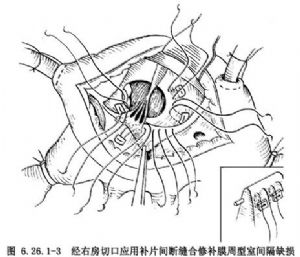

②膜周型缺損修補方法:應用補片間斷褥式縫合法:於三尖瓣環後下緣和隔瓣根部,應用間斷帶墊片褥式縫線縫合3~5針褥式縫線(圖6.26.1-3),分別穿過補片結紮,再順鐘向到後上方縫於心室漏斗褶與三尖瓣環結合處。若心室漏斗褶發育不全,在此處有時要用帶小墊褥式縫線1~2針直接縫於主動脈瓣環上,然後轉至室上嵴;下方轉移至竇部室間隔之右心室面,每針縫線均穿過補片相應部位,推下補片結紮縫線。缺損的其他部分可應用間斷帶墊片褥式縫合或連續縫合,完全閉合室間隔缺損(圖6.26.1-4)。